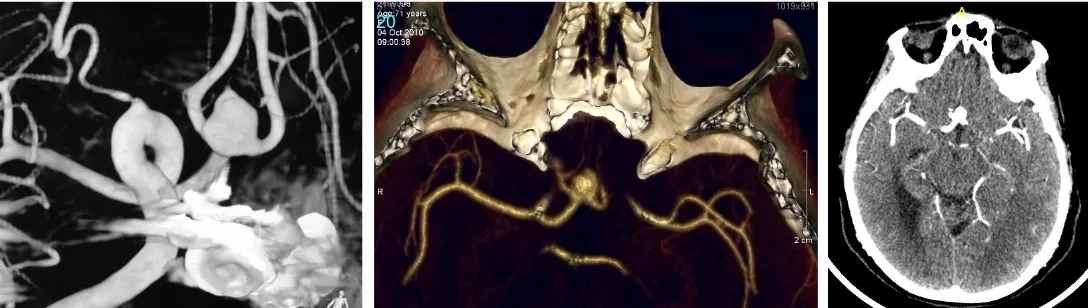

El diagnóstico se apoya en la tomografía computarizada (TAC) y la arteriografía cerebral.

El diagnóstico de la hemorragia subaracnoidea y del aneurisma causante se realiza en dos fases complementarias:

En primer lugar, se confirma la presencia de sangre en el líquido cefalorraquídeo. La prueba fundamental es la tomografía computarizada (TAC), que permite visualizar la sangre en el espacio subaracnoideo. Cuando existen dudas diagnósticas —por ejemplo, para diferenciarlo de una meningitis—, puede realizarse una punción lumbar que confirme la presencia de sangre en el LCR.

Una vez confirmada la hemorragia, es necesario identificar el aneurisma responsable. Para ello se emplean la angio-TAC (TAC con contraste vascular) y el estudio angiográfico cerebral (arteriografía), que no solo permiten localizar y caracterizar el aneurisma antes de la intervención, sino que también sirven para comprobar que el aneurisma se ha cerrado correctamente tras el tratamiento.